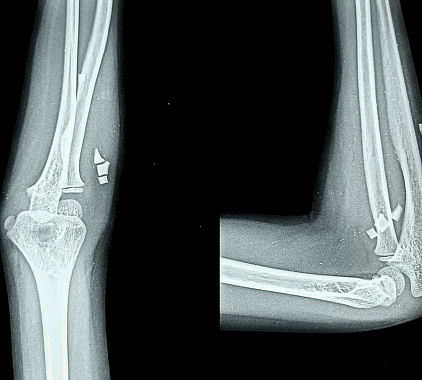

Рентгенографию локтевого сустава проводят в прямой и боковой проекциях. При получении снимка в прямой проекции больной находится боком к диагностическому столу, кладет руку ладонью вверх и разгибает ее в локтевом суставе. Чтобы получить изображения в боковой проекции, пациент остается в том же положении, руку размещает вниз ладонью и сгибает в локте под прямым углом. Для получения фотографий в аксиальной проекции изображения делают во время максимального сгибания руки в суставе, локоть при этом фиксируется подставкой.

Анализируя полученные рентгеновские снимки, врач оценивает состояние всех структур локтевого сустава, костей, рядом расположенных тканей (связки, синовиальная оболочка, капсула, сухожилия). Доктор изучает диаметр суставной щели, конгруэнтность суставных поверхностей. Сравнивая значения с нормой, специалист диагностирует разные патологии, определяет их характеристики: форма, локализация, распространенность, размеры, отличительные черты. Собрав все сведения, доктор пишет заключение.

С помощью рентгена локтевого сустава в двух проекциях можно обнаружить переломы костей, инородные тела, вывихи и подвывихи суставных поверхностей, трещины костных структур, артроз, остеомиелит, артрит, аномалии развития. Рентгенологическое обследование актуально в плане выявления воспалительных и инфекционных поражений, костных разрастаний, кальцинатов, уплотнений и новообразований, разрыва связок, остеопороза.